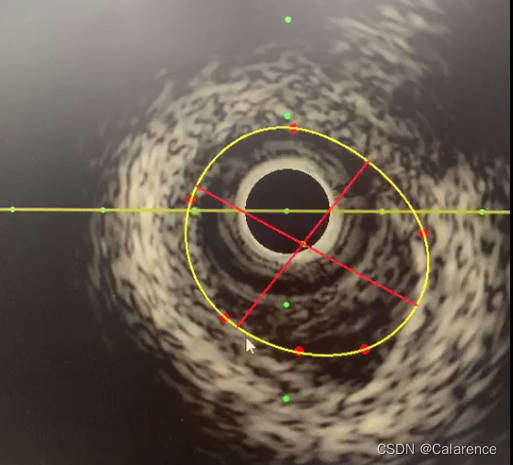

2.计算长轴和短轴:采用fitEllipse得到拟合的椭圆cv::RotatedRect,根据中心点和Ellipse的宽高和角度得到长轴和短轴的坐标点,但是得到的点有时候不在贝塞尔曲线上,无法满足要求,原因是贝塞尔曲线点得到的拟合圆已经脱离了曲线本身。

考虑到长轴或者短轴,经过中心点,则计算得到最小和最大的距离点,并和中心点组合一条直线,该直线定会和曲线上相交,从而得到长轴或短轴对应的另外一点。计算过程中要排除自身点的影响。

另外一点计算策略为:根据直线的斜率判断,已知点和中心点,另一点和中心点所计算得到的斜率差值最小,则为长轴或者短轴上另外一点。